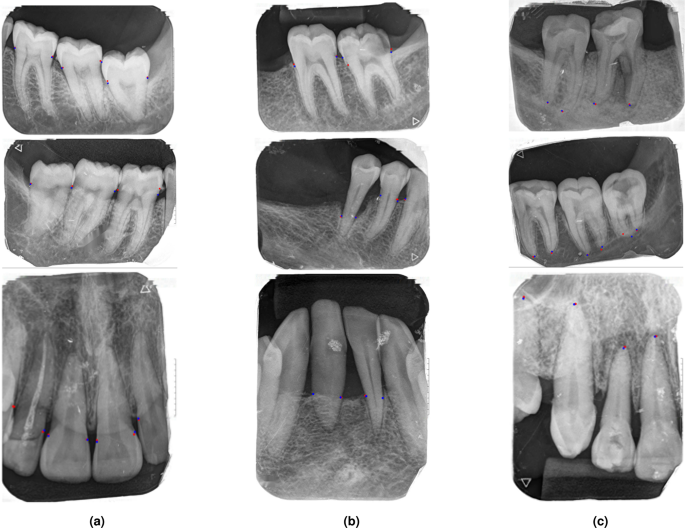

Comparison of ground truth and predicted key points for tooth analysis: a cemento-enamel junction (CEJ) points; b alveolar bone level and tooth intersection points; c apex points. Blue points indicate ground truth, red points indicate predictions.

To assess whether the performance differences between Keypoint R-CNN and YOLOv8 Pose were statistically significant, we computed paired p-values on the test set using per-image AP\(_{50{:}95}\) (OKS) scores obtained from YOLOv8 Pose, with Keypoint R-CNN as the reference model. The results showed statistically significant differences across all keypoints, with p-values of \(3.76 \times 10^{-9}\) for CEJ, \(2.55 \times 10^{-5}\) for the intersection point between the tooth boundary and the alveolar bone level, and \(4.01 \times 10^{-2}\) for the apex. Figure 8a shows example predictions and ground truth annotations for CEJ, Fig. 8b for the intersection point, and Fig. 8c for the apex.

Keypoint R-CNN and YOLOv8x-Pose56 were experimented to detect main types of keypoints. For evaluation, , Object Keypoint Similarity (OKS) was used as the threshold to evaluate the key points. OKS is considered the IoU in keypoints56. By considering variables such as scale, unlabeled keypoints, and annotation ambiguity, OKS provides a standardized metric for comparing predicted keypoints against ground truth57. Both models were trained under identical settings, except for the learning rate and scheduler (the initial learning rate was 0.00001, and a Cosine learning rate were used for YOLOv8x-Pose).

The results are presented in Table 3. On the test dataset, Keypoint R-CNN achieved AP50:95 scores of 0.954 for CEJ, 0.912 for intersection point of tooth boundary and alveolar bone level, and 0.815 for apex points. YOLOv8x-Pose achieved AP50:95 scores of 0.828, 0.813, and 0.498 for the same keypoints, respectively.